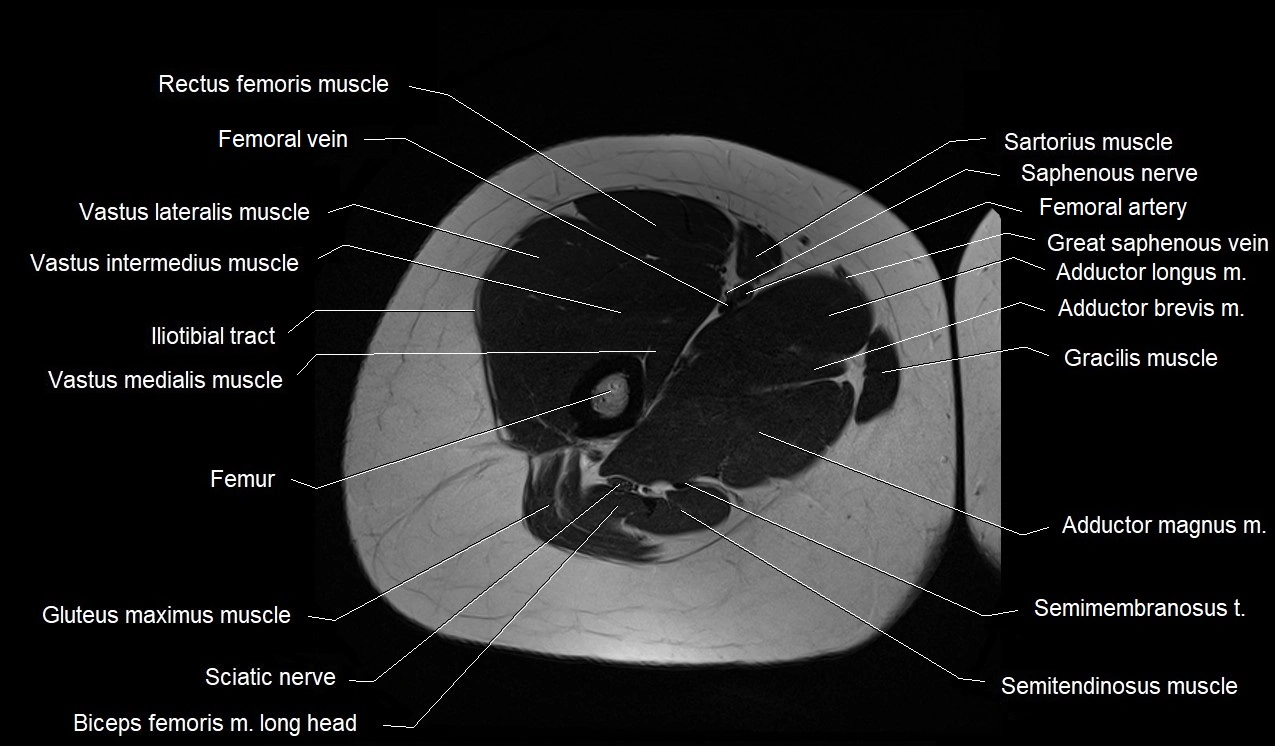

- Adductor brevis muscle

- Adductor longus muscle

- Adductor magnus muscle

- Biceps femoris muscle (Long head)

- Femoral vein

- Femur

- Gracilis muscle

- Iliotibial tract

- Rectus femoris muscle

- Saphenous nerve

- Sartorius muscle

- Semimembranosus muscle

- Semitendinosus muscle

- Tibial nerve

- Vastus intermedius muscle

- Vastus lateralis muscle

- Vastus medialis muscle